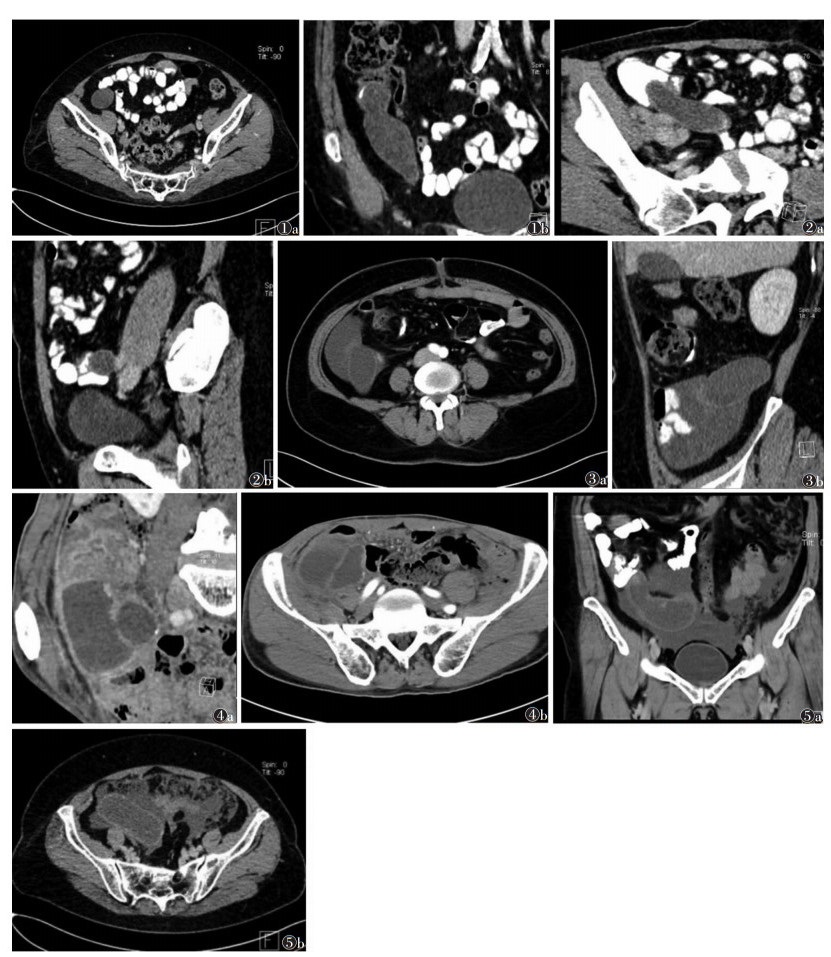

1 AM的病理及临床特点AM是指各种原因所引起的阑尾腔阻塞,使阑尾黏膜分泌的黏液不能及时排出,造成黏液不断在阑尾腔内蓄积,导致阑尾囊状扩张,形成囊性肿块。AM在临床上相对少见,占阑尾切除原因的0.1%~0.4%[1],患者年龄通常 > 50岁。AM根据病理结果可分为4种类型:①非肿瘤性囊肿,包括单纯性囊肿(图 1)和黏膜增生;②黏液囊腺瘤(图 2);③低级别阑尾黏液性肿瘤(low grade appendiceal mucinous neoplasm,LAMN)(图 3,4);④黏液囊腺癌(图 5)。

| 图 1 女,阑尾单纯性黏液囊肿 图 1a CT平扫示右下腹囊性肿块 图 1b 增强扫描MPR示阑尾区长条状囊性肿块,伴弧形钙化,囊壁均匀,光滑一致,未见明显强化 图 2 女,阑尾黏液囊腺瘤 图 2a CT平扫示右下腹长条形囊性肿块伴弧形钙化 图 2b 增强扫描MPR示右下腹阑尾区囊性肿块,囊壁均匀,光滑一致,呈轻度强化 图 3 女,52岁,阑尾低级别黏液性肿瘤 图 3a CT图像示右下腹管状囊性肿块伴壁结节和腹膜假黏液瘤 图 3b 增强扫描矢状位示阑尾区囊性肿块伴壁结节,腹腔积液,囊壁粗糙、明显强化 图 4 男,阑尾低级别黏液性肿瘤 图 4a CT平扫示右下腹囊性肿块伴点状钙化和分隔 图 4b 增强扫描囊肿内可见分隔,囊壁厚薄不均匀、粗糙、明显强化 图 5 女,阑尾黏液囊腺癌 图 5a CT平扫示右下腹长椭圆形囊性肿块伴点状钙化,腹膜增厚呈结节状或饼状 图 5b 增强扫描示阑尾区囊性肿块伴壁结节,囊壁厚薄不均匀、粗糙、较明显强化,伴腹腔积液 |